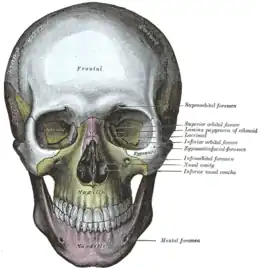

En anatomie, les orbites sont les parties du squelette crânien qui constituent les deux cavités orbitaires dans lesquelles les yeux et leurs appendices sont situés.

Elles sont situées au-dessus du massif facial.

Structure

L'orbite forme une cavité profonde pyramidale quadrangulaire de base antérieure située de chaque côté de la cavité nasale.

La base de la pyramide forme l'orifice orbitaire limité par quatre bords : les bords supra-orbitaire, infra-orbitaire, latéral et médial.

Les quatre faces de la pyramide forment les parois supérieure, inférieure, latérale et médiale de l'orbite.

L'orbite humaine est formée par les prolongements ou les parties de sept os :

- l'os frontal,

- l'os zygomatique,

- l'os maxillaire,

- l'os sphénoïde,

- l'os palatin,

- l'os ethmoïde,

- l'os lacrymal.